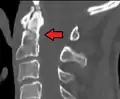

Type 3 odontoid fracture